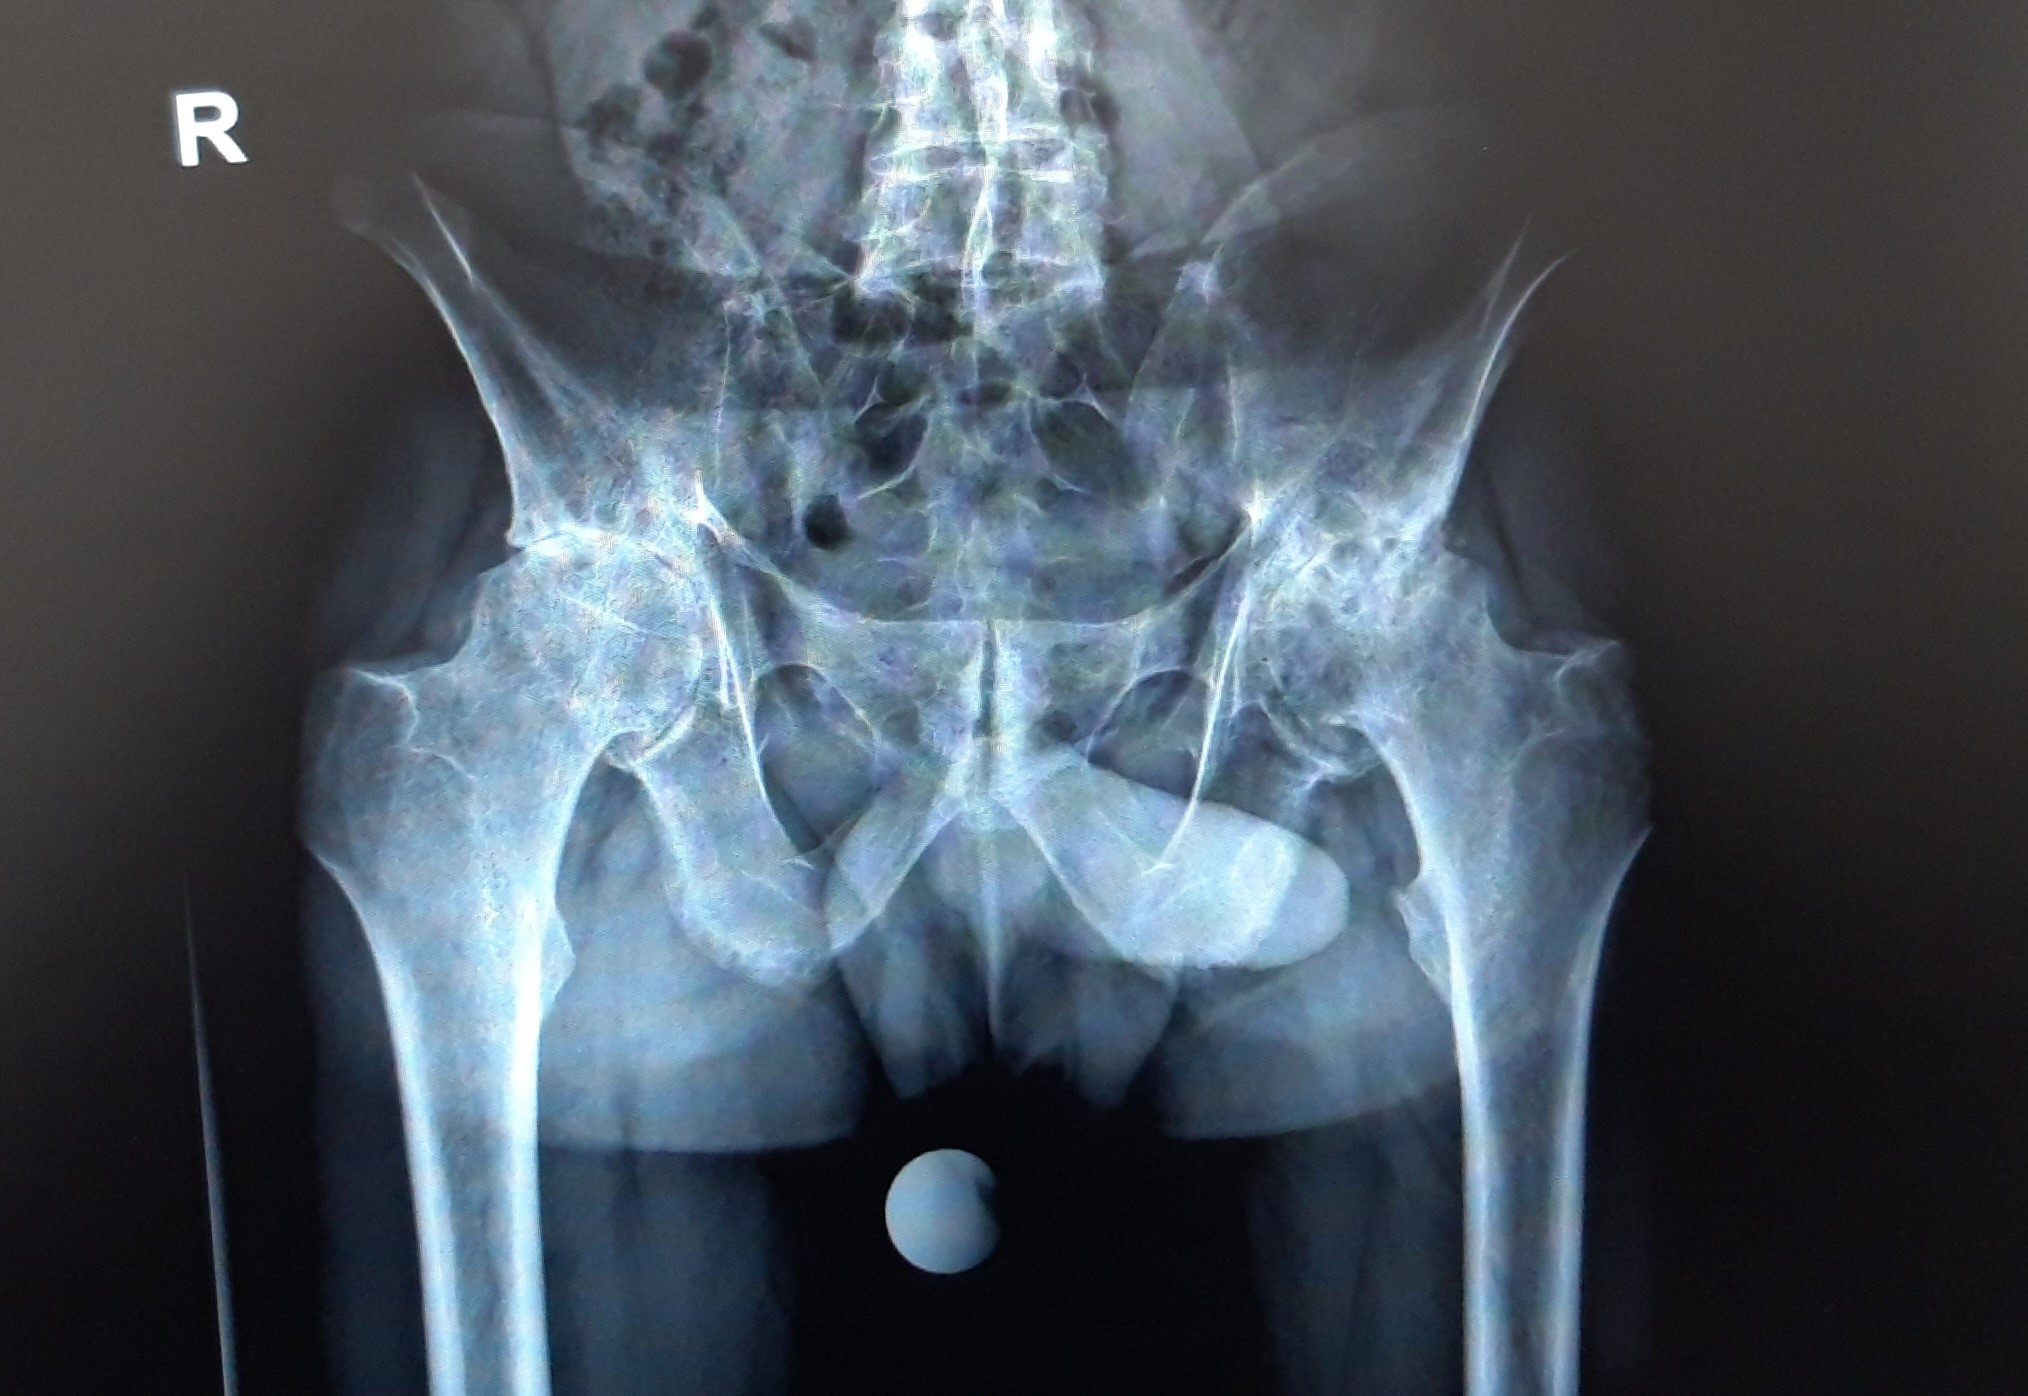

նկար 3․ Նախքան վիրահատությունը նկար 4․ Վիրահատությունից 5 տարի անց